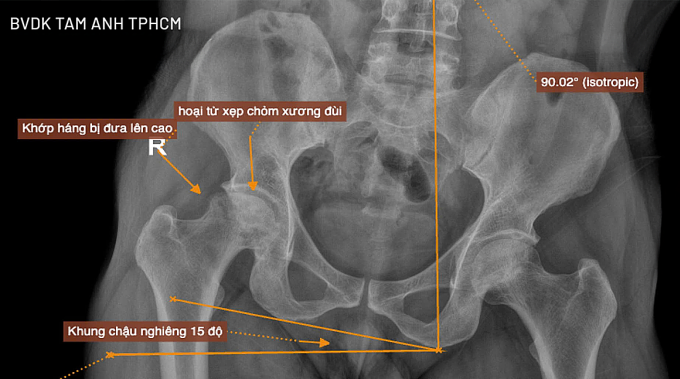

Kết quả chụp X-quang tại Bệnh viện Đa khoa Tâm Anh TP HCM cho thấy ông Hưng bị hoại tử chỏm xương đùi giai đoạn cuối, chỏm xương đùi xẹp và biến dạng, ổ cối thoái hóa một phần, xương chậu nghiêng 15 độ, khi quan sát bằng mắt thường chân phải ngắn hơn chân trái khá nhiều.

Phim chụp X-quang cho thấy khớp háng bên phải bị đẩy lên cao, khiến xương chậu nghiêng nhiều. Ảnh: Bệnh viện Đa khoa Tâm Anh